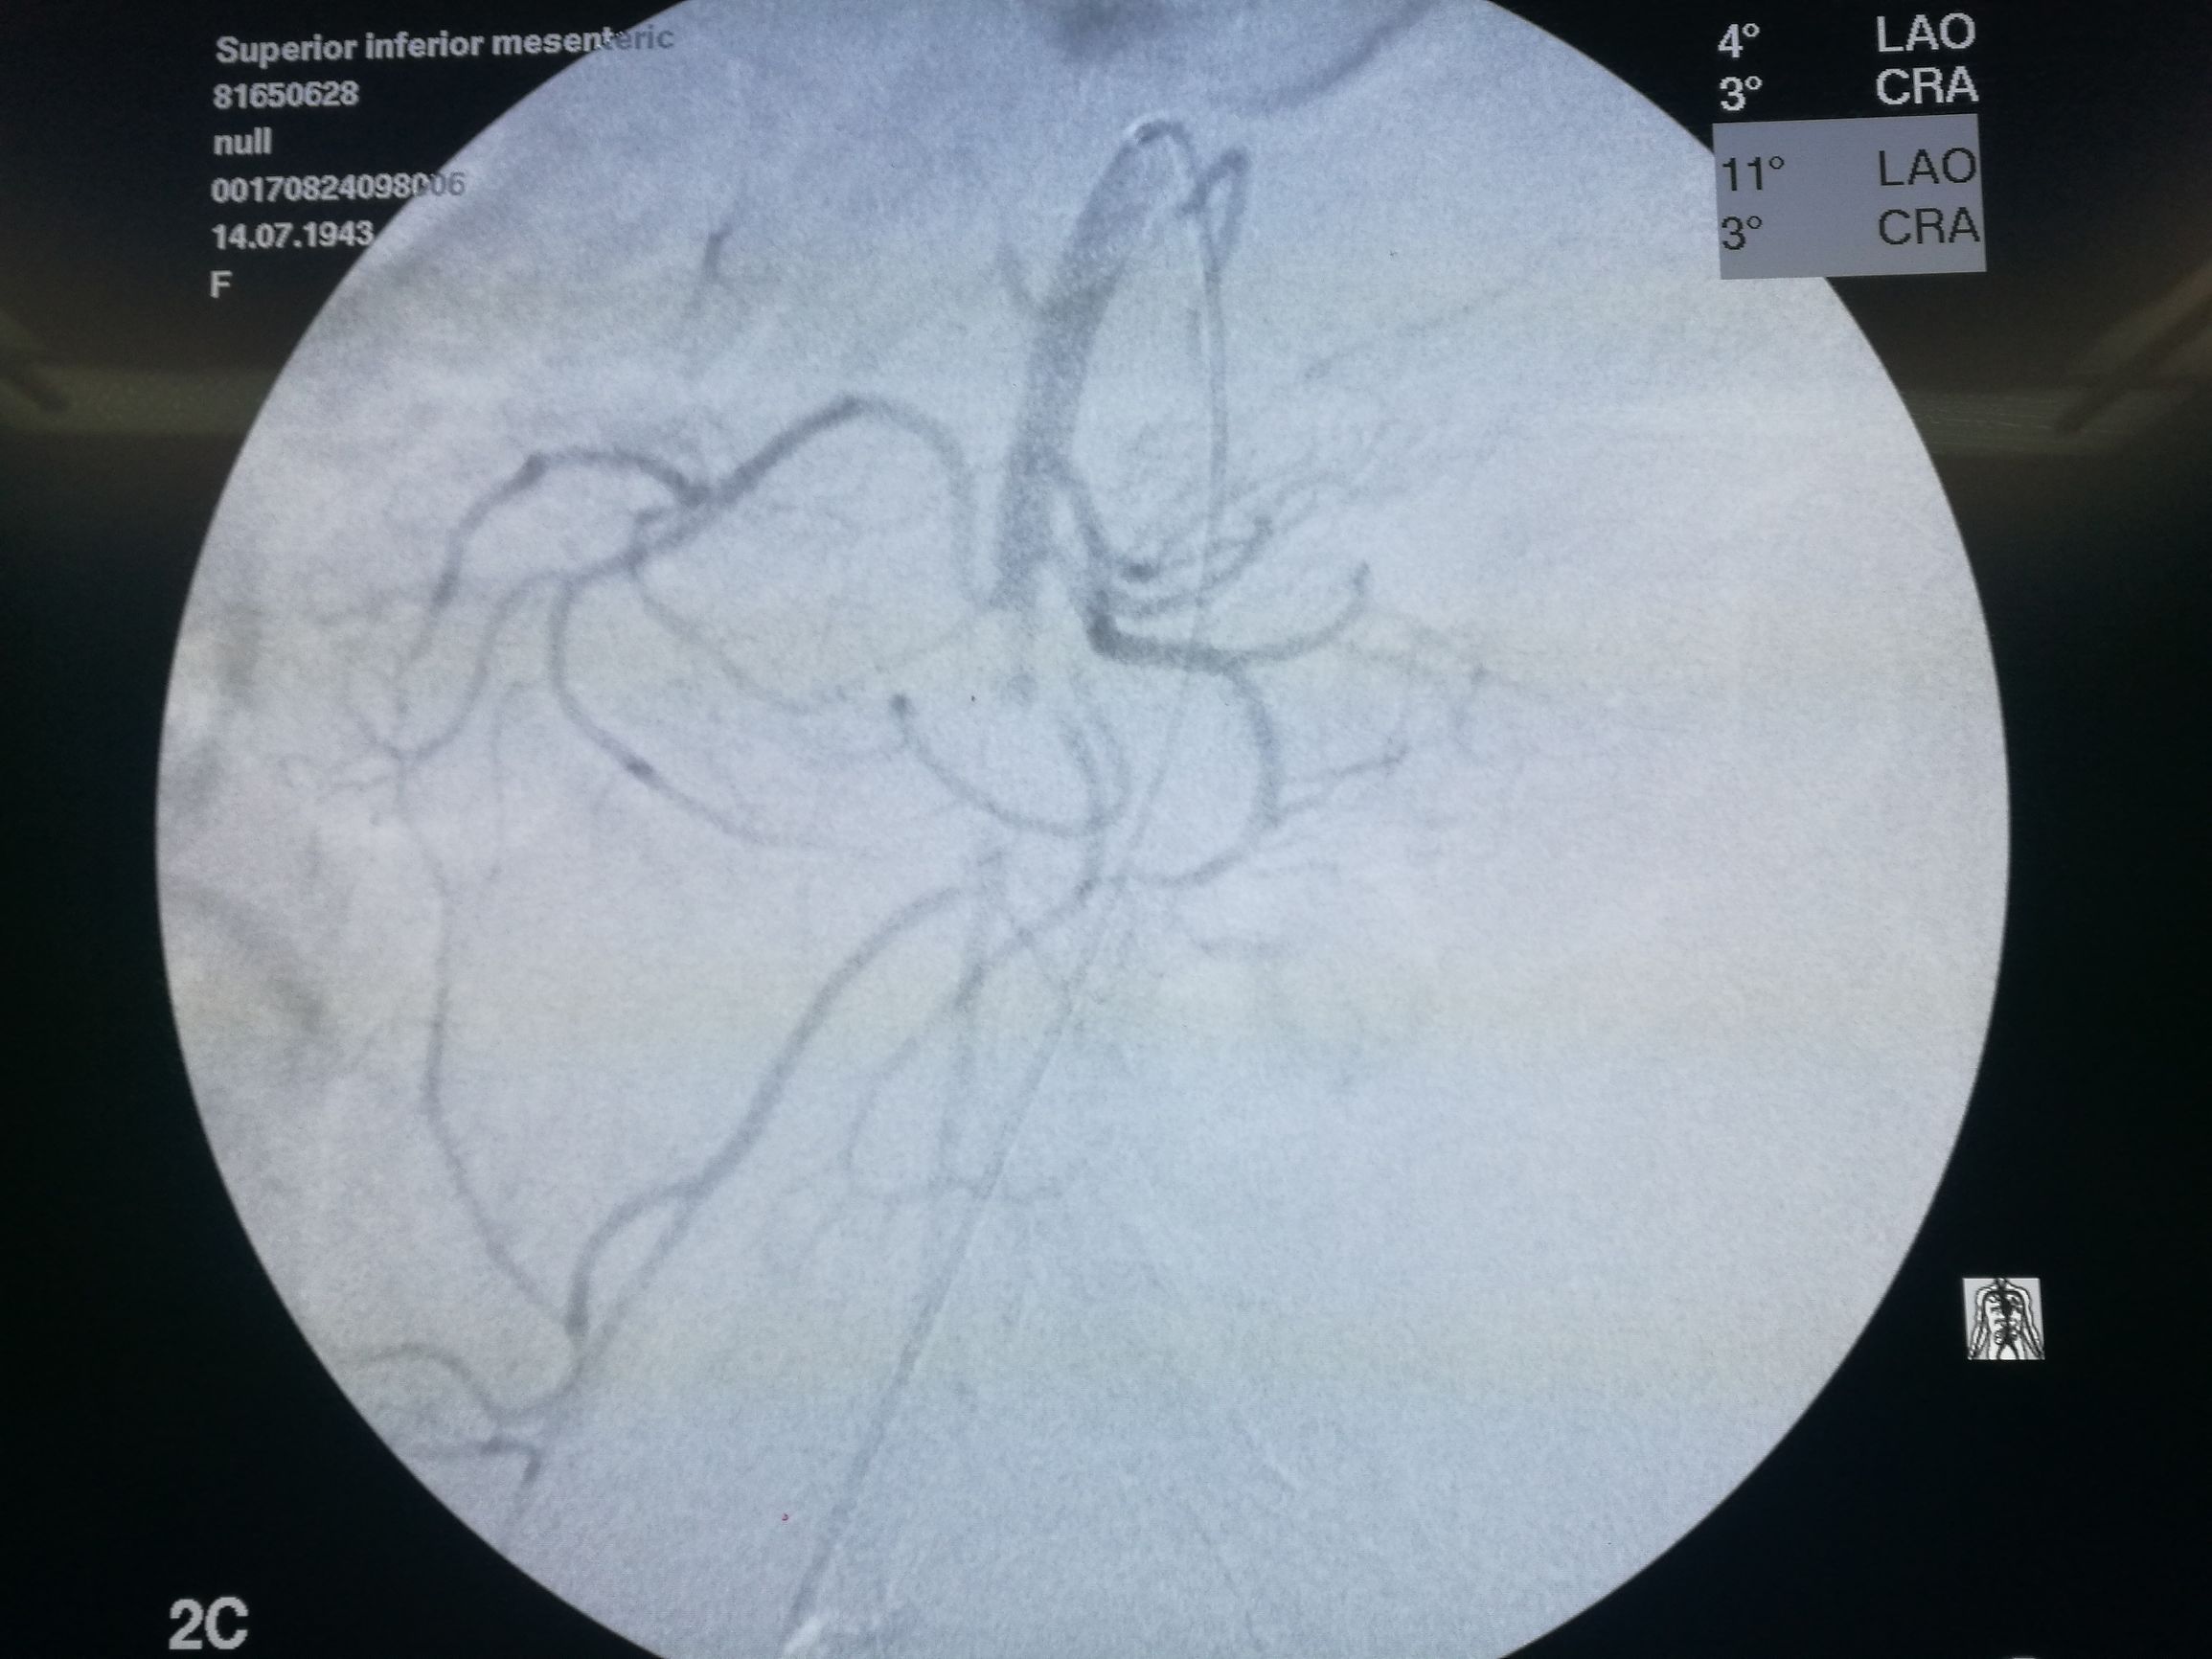

在局麻下经右侧股动脉穿刺,导管选入肠系膜上动脉造影,可见腔内充盈缺损(图3)。

图3. 肠系膜上动脉造影,可见管腔内充盈缺损,局部主干中断